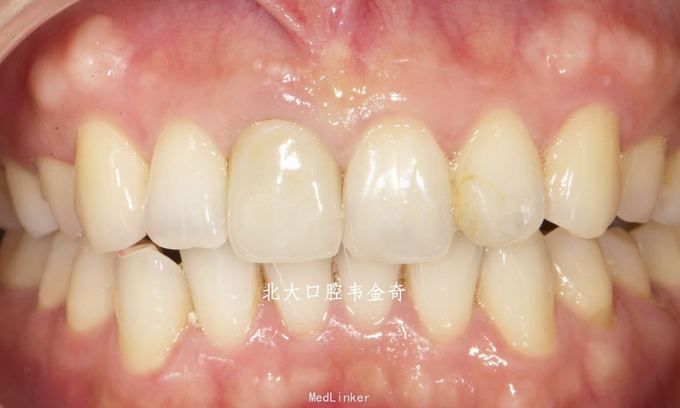

诊断:11牙体缺损,牙冠变色。 处理:建议桩核冠修复。常规操作完成纤维桩树脂核,以及铸瓷冠修复。

讨论:对于这种重度变色的牙齿,铸瓷冠由于具有较高的通透性遮色能力差,修复效果不好。选用遮色能力更强的氧化锆冠会好很多。 另一方面,根管治疗后多年,牙体重度变色,说明牙体组织内部结构在崩解,质地变差。在治疗过程中也感觉到牙体组织比正常的要软。因此告知患者这个牙齿发生折断的可能性比较大。交流的时候着重提到这个问题。患者处于这种考虑选择相对便宜的铸瓷冠而不是氧化锆冠。 虽然修复效果不够完美,但改善的幅度较大,患者仍比较满意。